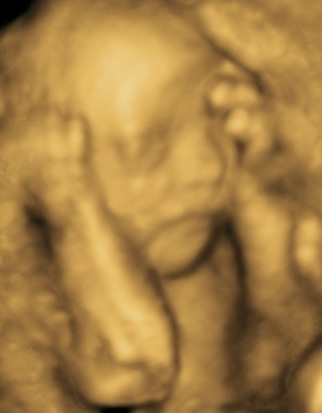

Contamos con gran variedad de estudios como abdomen, pélvico, tiroides, obstétrico 3D y 4D, protocolos maternofetales, estructural, entre otros.

MATERNO FETAL

PERFIL BIOFÍSICO FETAL